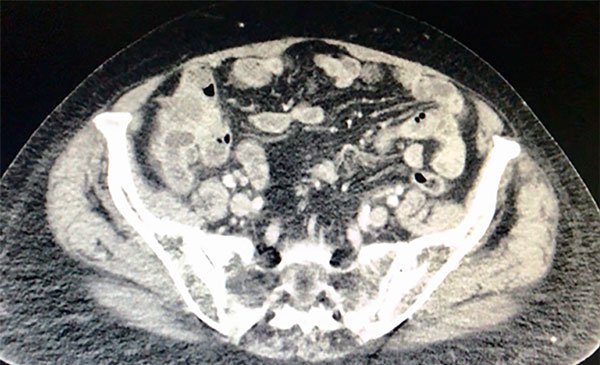

La TAC del abdomen y pelvis muestra engrosamiento parietal circunferencial e irregular del ciego. Se asocia a cambios sutiles en la densidad de los planos grasos adyacentes, ingurgitación de los vasos sanguíneos regionales y dos adenomegalias con centro hipodenso atribuible a necrosis en el territorio ileocólico, la mayor de 13 mm (Figs. 2 y 3).

Figura 3: TAC del abdomen donde se observa la relación de la formación tumoral con la pared abdominal anterior.